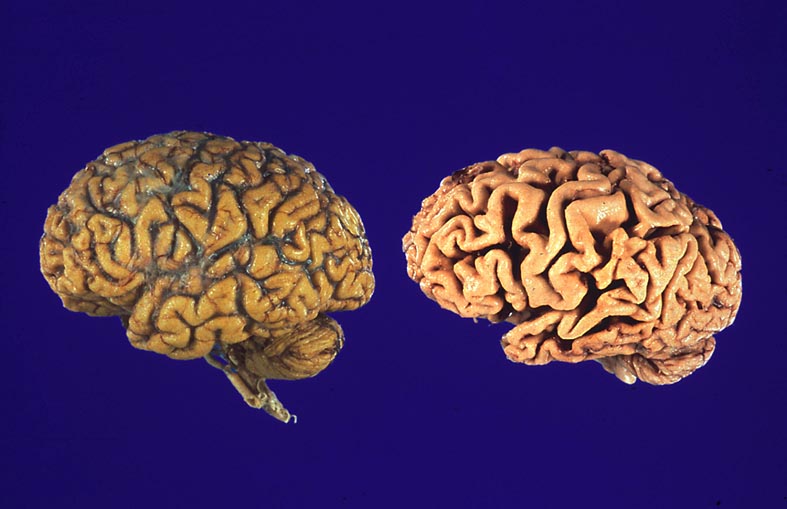

PathoPic – image database / PathoPic ID 4973 - Morbus Alzheimer

Morbus Alzheimer

Links im Bild ein normales Hirn. Rechts im Bild das Hirn eines Alzheimerkranken mit ausgeprägter Atrophie der Gyri und verbreiterten Sulci. Beim Alzheimerhirn sind die Leptomeningen entfernt worden.

Demenz seit 9 Jahren.